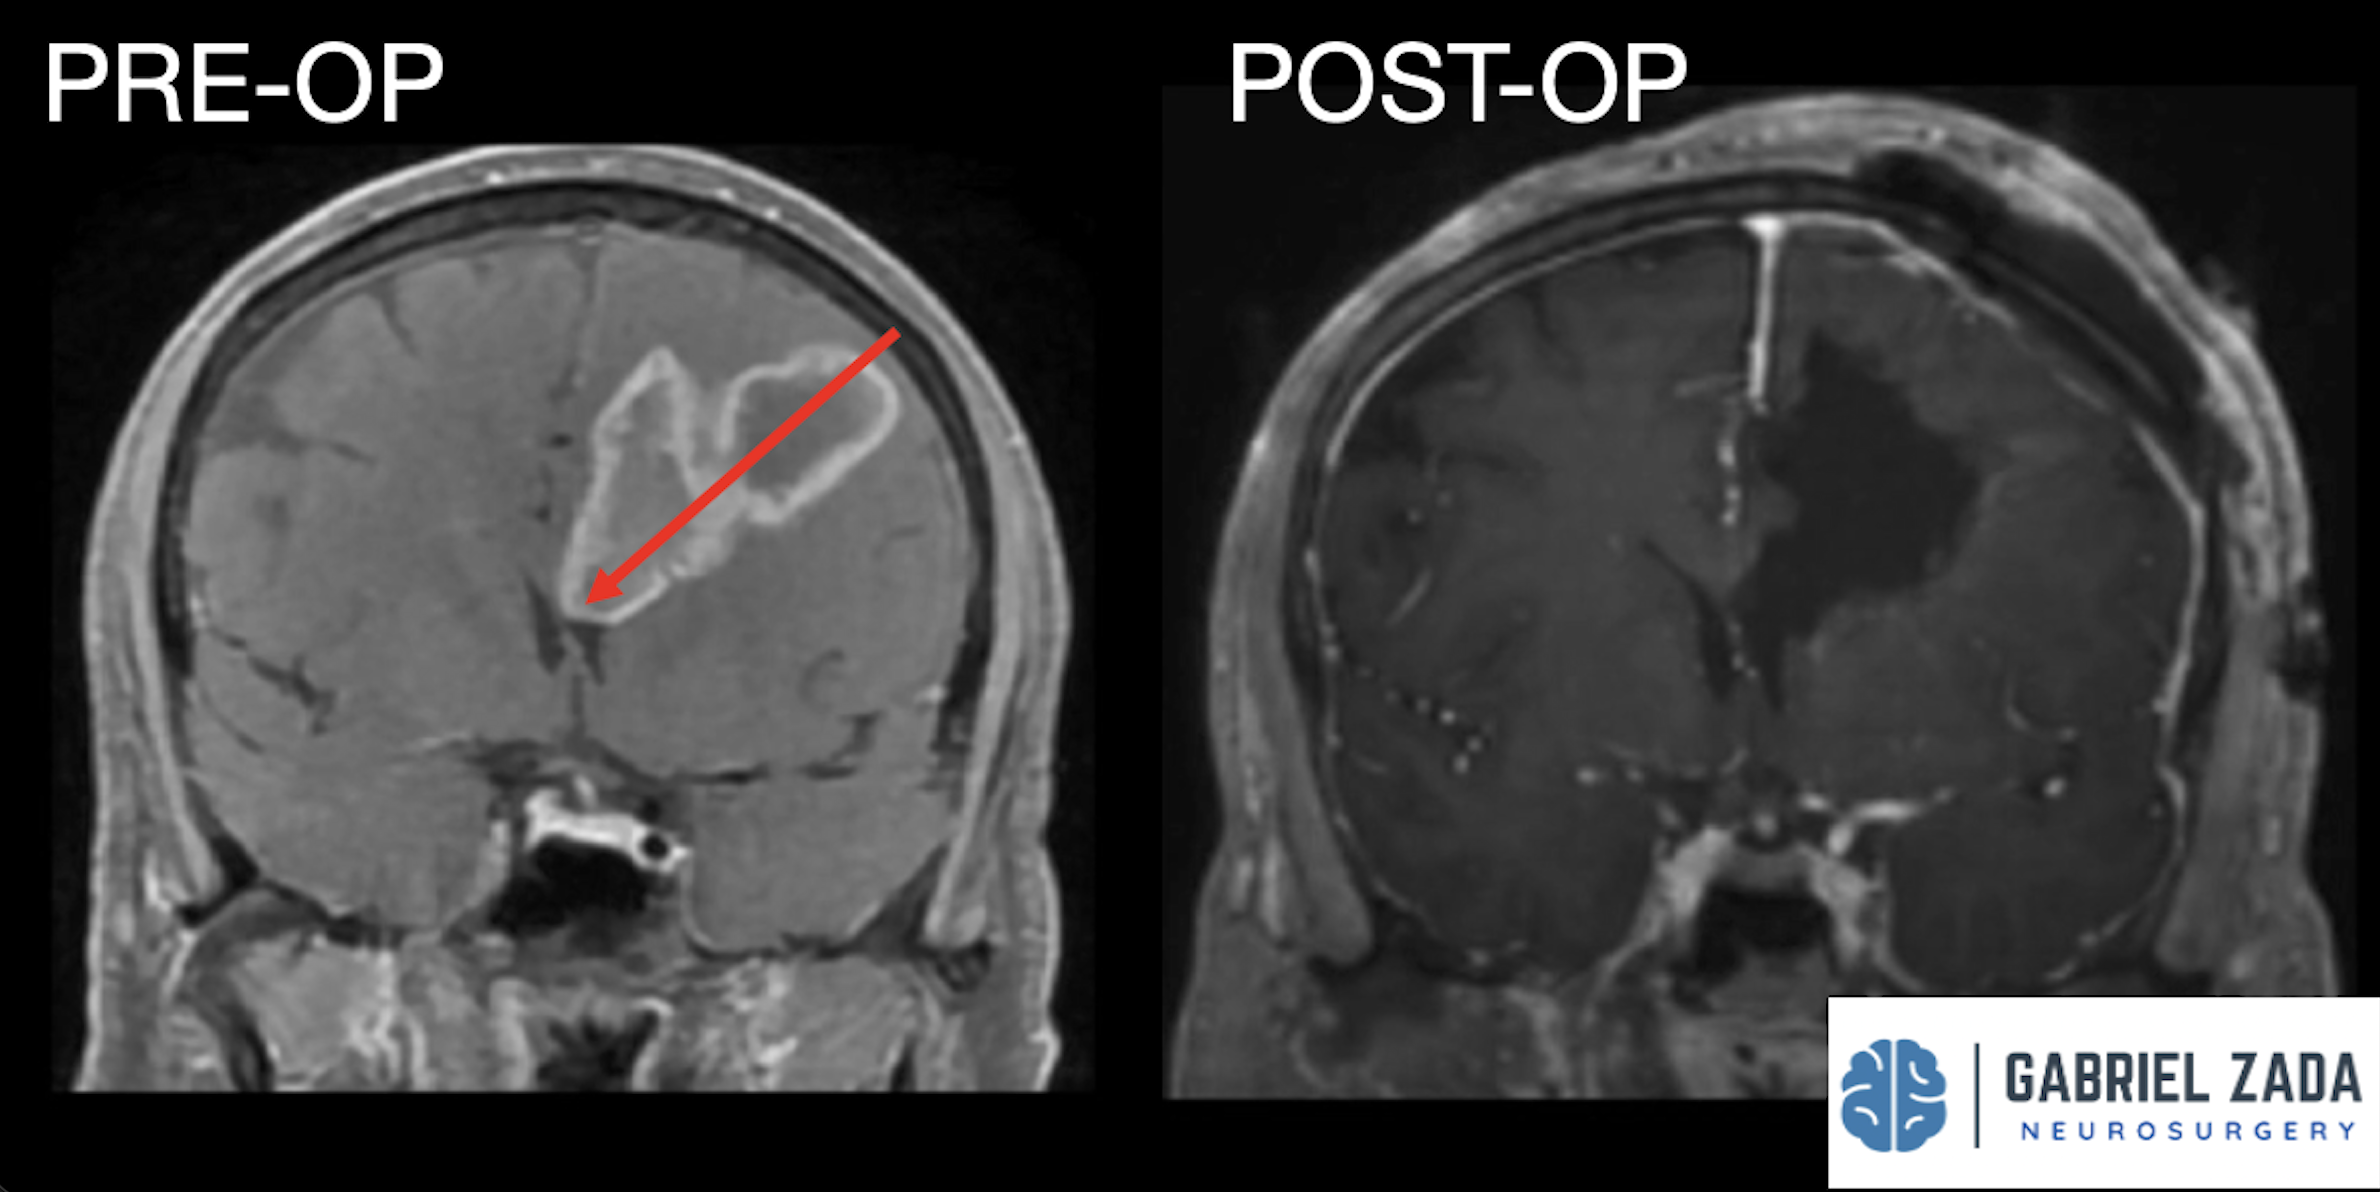

Explore this comprehensive gallery featuring pre‑ and post‑operative imaging of patients with skull‑base tumors treated by Gabriel Zada, MD, MS, FAANS, FACS. These cases highlight Dr. Zada’s expertise in advanced neurosurgical techniques and outcomes.

*Representative cases shown for educational purposes. All images de-identified. Individual results vary.